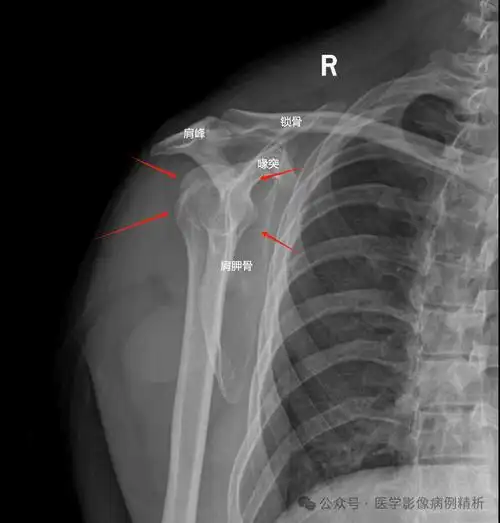

如何拍出标准的肩关节正位 大家看图

肩关节x线检查体位大全

📸肩关节x线摄影:前后位与侧位详解